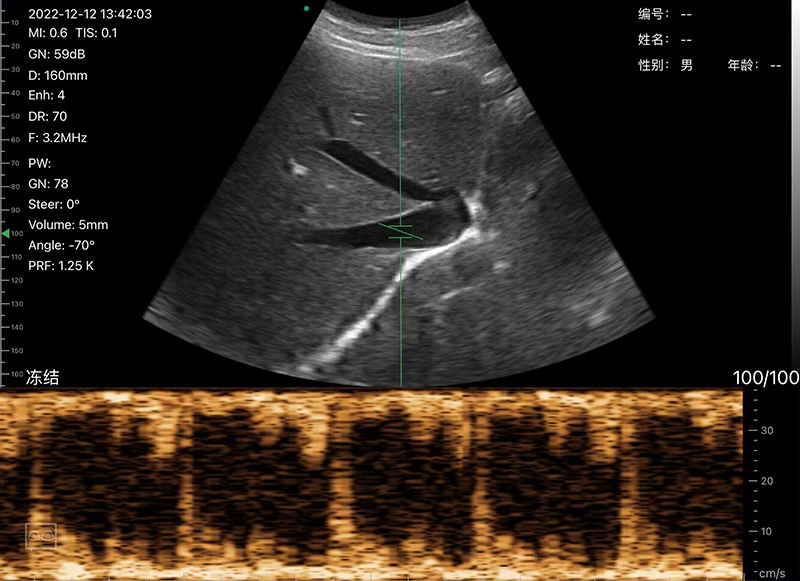

• Scan mode: Electronic Array Convex scanning

• Frequency: Convex probe 3.2/5.0MHz

• Display mode: B, B/M, Color, PDI, PW